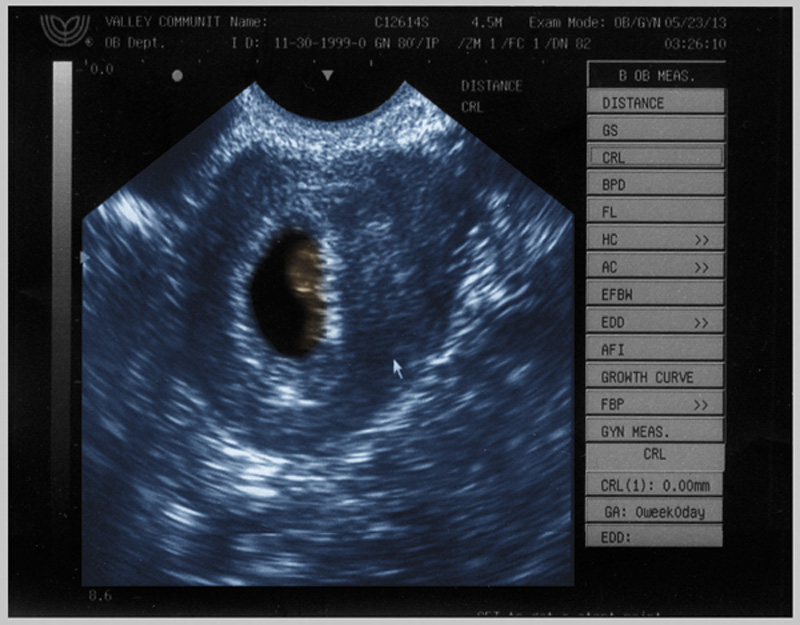

9:09 PM, Thursday, May 23rd, 2013:

Married on 1200, Pregnant on 1210, First Baby's First Video on 1220? Second Baby's First Video 120 entries later. That's a lot of 0s, 1s and 2s. :-)

...but, the first ultrasound kinda sucks in comparison to the coolness that's coming. It's nothing personal to the kid, OBVIOUSLY, but man the other video blew my ever-loving mind. However, this does mark our kid's official introduction to The Journey. Vienna is 1220, he/she's 1340. That's just really cool. This baby, too, gets a poop picture just like Vienna!